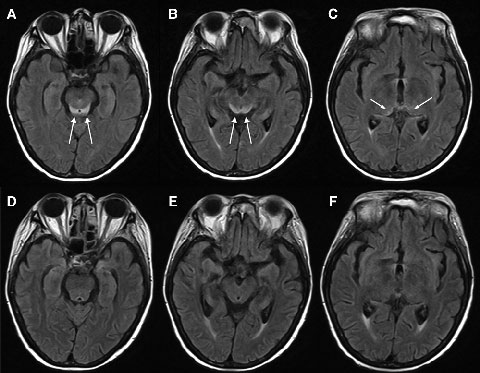

Electroencephalography showed generalised slowing without focal features. Magnetic resonance imaging (MRI) of the patient’s brain revealed symmetrical changes of high signal in the periaqueductal grey matter, superior colliculi and medial thalami, most evident on the fluid-attenuated inversion recovery (FLAIR) sequences (Box 1, A–C). These symmetrical periventricular changes were consistent with typical findings recently described for Wernicke’s encephalopathy.1

Given the clinical history of dietary deprivation and colitis, together with the typical radiological changes, a diagnosis of Wernicke’s encephalopathy was strongly suspected. Hence, intravenous thiamine 500 mg three times a day was administered, after which the patient made a dramatic clinical and radiological recovery (Box 1, D–F) over a period of about 7 days. Despite this, her pretreatment (Day 15) blood thiamine pyrophosphate level, measured using high-performance liquid chromatography, was eventually reported as being normal (136 nmol/L [reference range, 67–200 nmol/L]). However, given her clinical history, the changes noted on MRI and the dramatic improvement in her condition with thiamine, the diagnosis of Wernicke’s encephalopathy remained the most likely explanation.

In the past decade, magnetic resonance imaging (MRI) has been recognised as a useful adjunct in Wernicke’s encephalopathy diagnosis.6 Wernicke’s encephalopathy typically causes symmetrical alterations in MRI signal intensity (increased on fluid-attenuated inversion recovery [FLAIR] images) in the periventricular regions of the brain, including the medial thalami, periaqueductal grey matter, tectal plate (inferior and superior colliculi), and mamillary bodies.1,7 It has been suggested that MRI changes which occur in alcoholic and non-alcoholic patients with Wernicke’s encephalopathy may differ, with contrast enhancement of the mamillary bodies and thalami occurring more frequently in the alcoholic patients, suggesting that these areas may be selectively susceptible to alcohol toxicity.7